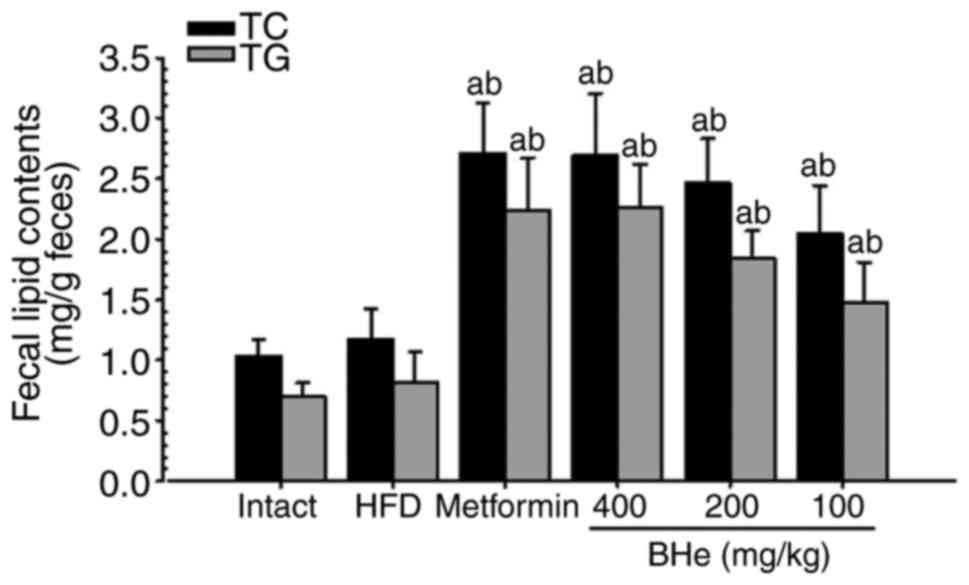

A significant increase in the fecal TC and TG levels

was observed in all treatment groups; however, the changes in the

HFD control group were not significant. Specifically, all

BHe-treated groups exhibited a clear dose-dependent increase in the

fecal TC and TG levels compared with in the HFD control group

(Fig. 2). The fecal TC content

increased by 13.04% in the HFD control group, with changes of

131.20, 74.57, 110.26 and 130.34% observed in metformin (250 mg/kg)

and BHe (400, 200 and 100 mg/kg)-treated groups compared with in

the HFD control group, respectively. The fecal TG content was

increased by 16.25% in the HFD control group, with changes of

174.65, 81.57, 127.04 and 177.57% observed in the metformin (250

mg/kg) and BHe (400, 200 and 100 mg/kg)-treated groups,

respectively.